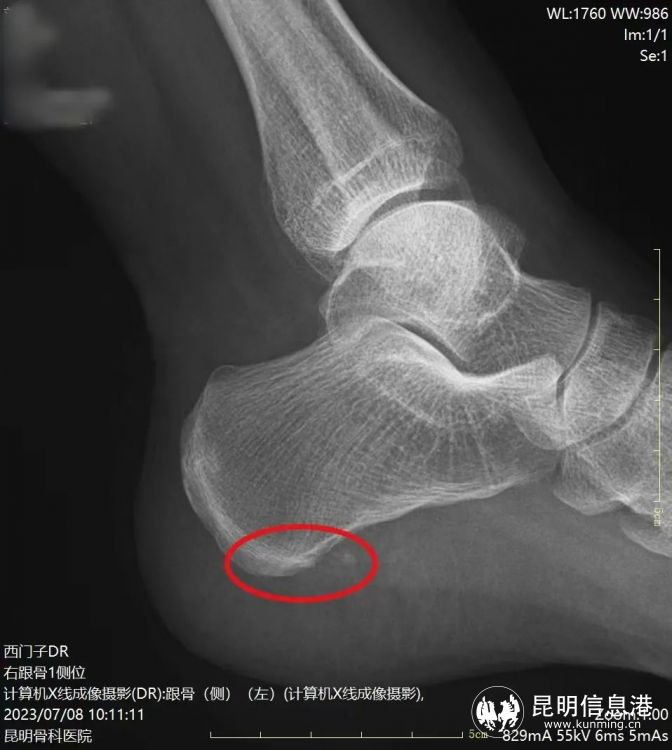

術(shù)后骨刺消失

“經(jīng)檢查發(fā)現(xiàn)劉女士不僅左足跟有跟骨骨刺,雙足還有足底筋膜炎,本次微創(chuàng)手術(shù)只需在患者足內(nèi)側(cè)跟骨前結(jié)節(jié)處兩側(cè)各取一個0.2-0.5cm的小孔,建立鏡下手術(shù)工作通道,就能在可視下磨除跟骨骨刺,筋膜松解,處理炎癥組織。”昆明骨科醫(yī)院手足顯微外科主任李海波介紹說,這種新型的微創(chuàng)治療手段對比起傳統(tǒng)的治療來講有很大的優(yōu)勢,微創(chuàng)損傷小、恢復(fù)快、手術(shù)疼痛輕等特點,傳統(tǒng)的跟痛癥手術(shù)通常從跟骨內(nèi)側(cè)長斜形切口,長約5厘米,典型的“小手術(shù)、大切口”。